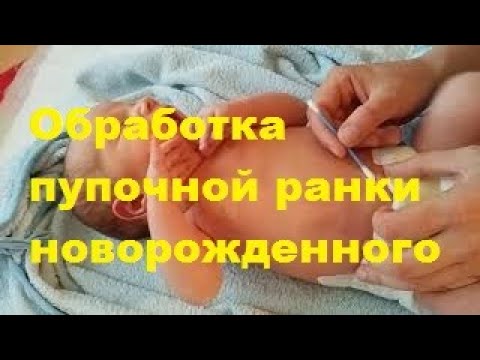

Обработка пупочной ранки новорожденного

Обработка пуповины

Обработка пуповины

Уход за пупком новорожденного